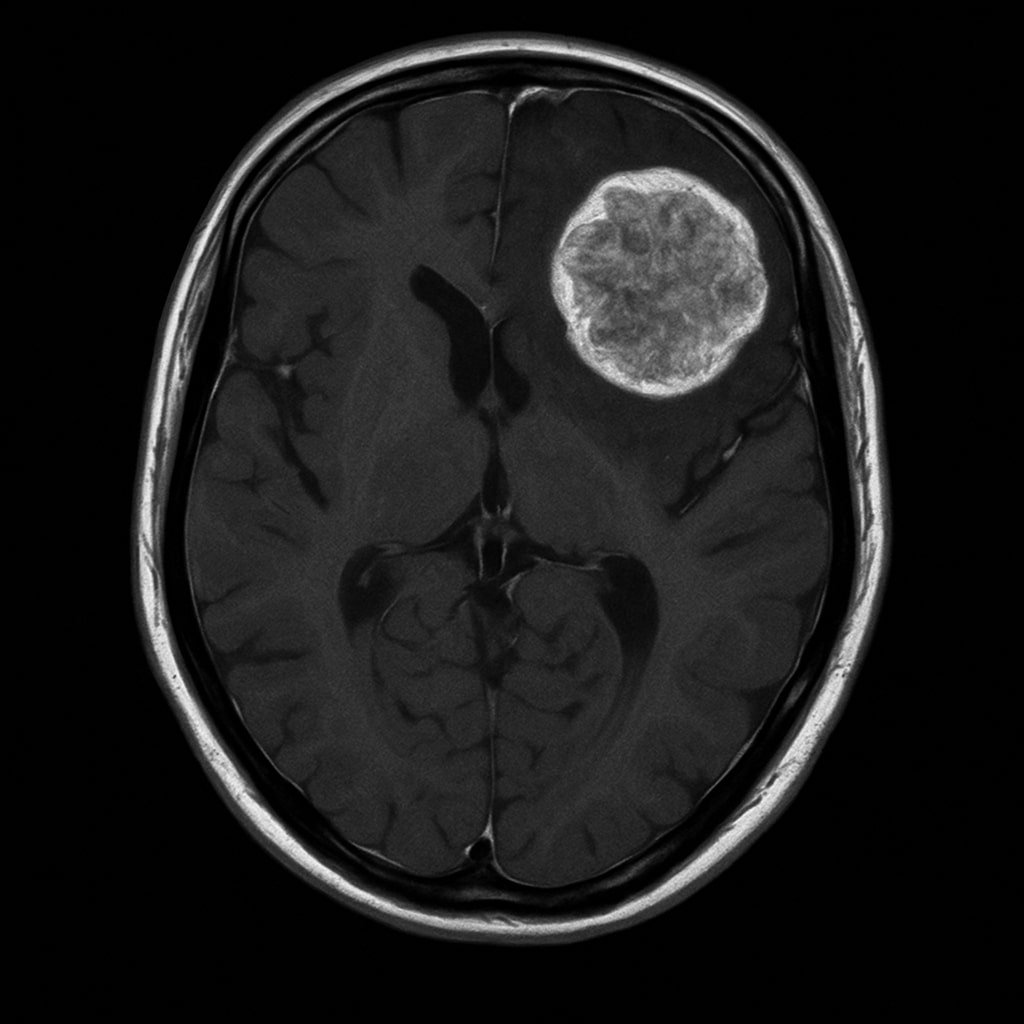

Glioblastoma Multiforme

Meningioma

Astrocytoma

Arteriovenous Malformations (AVM)

Cavernomas

Pituitary Tumors